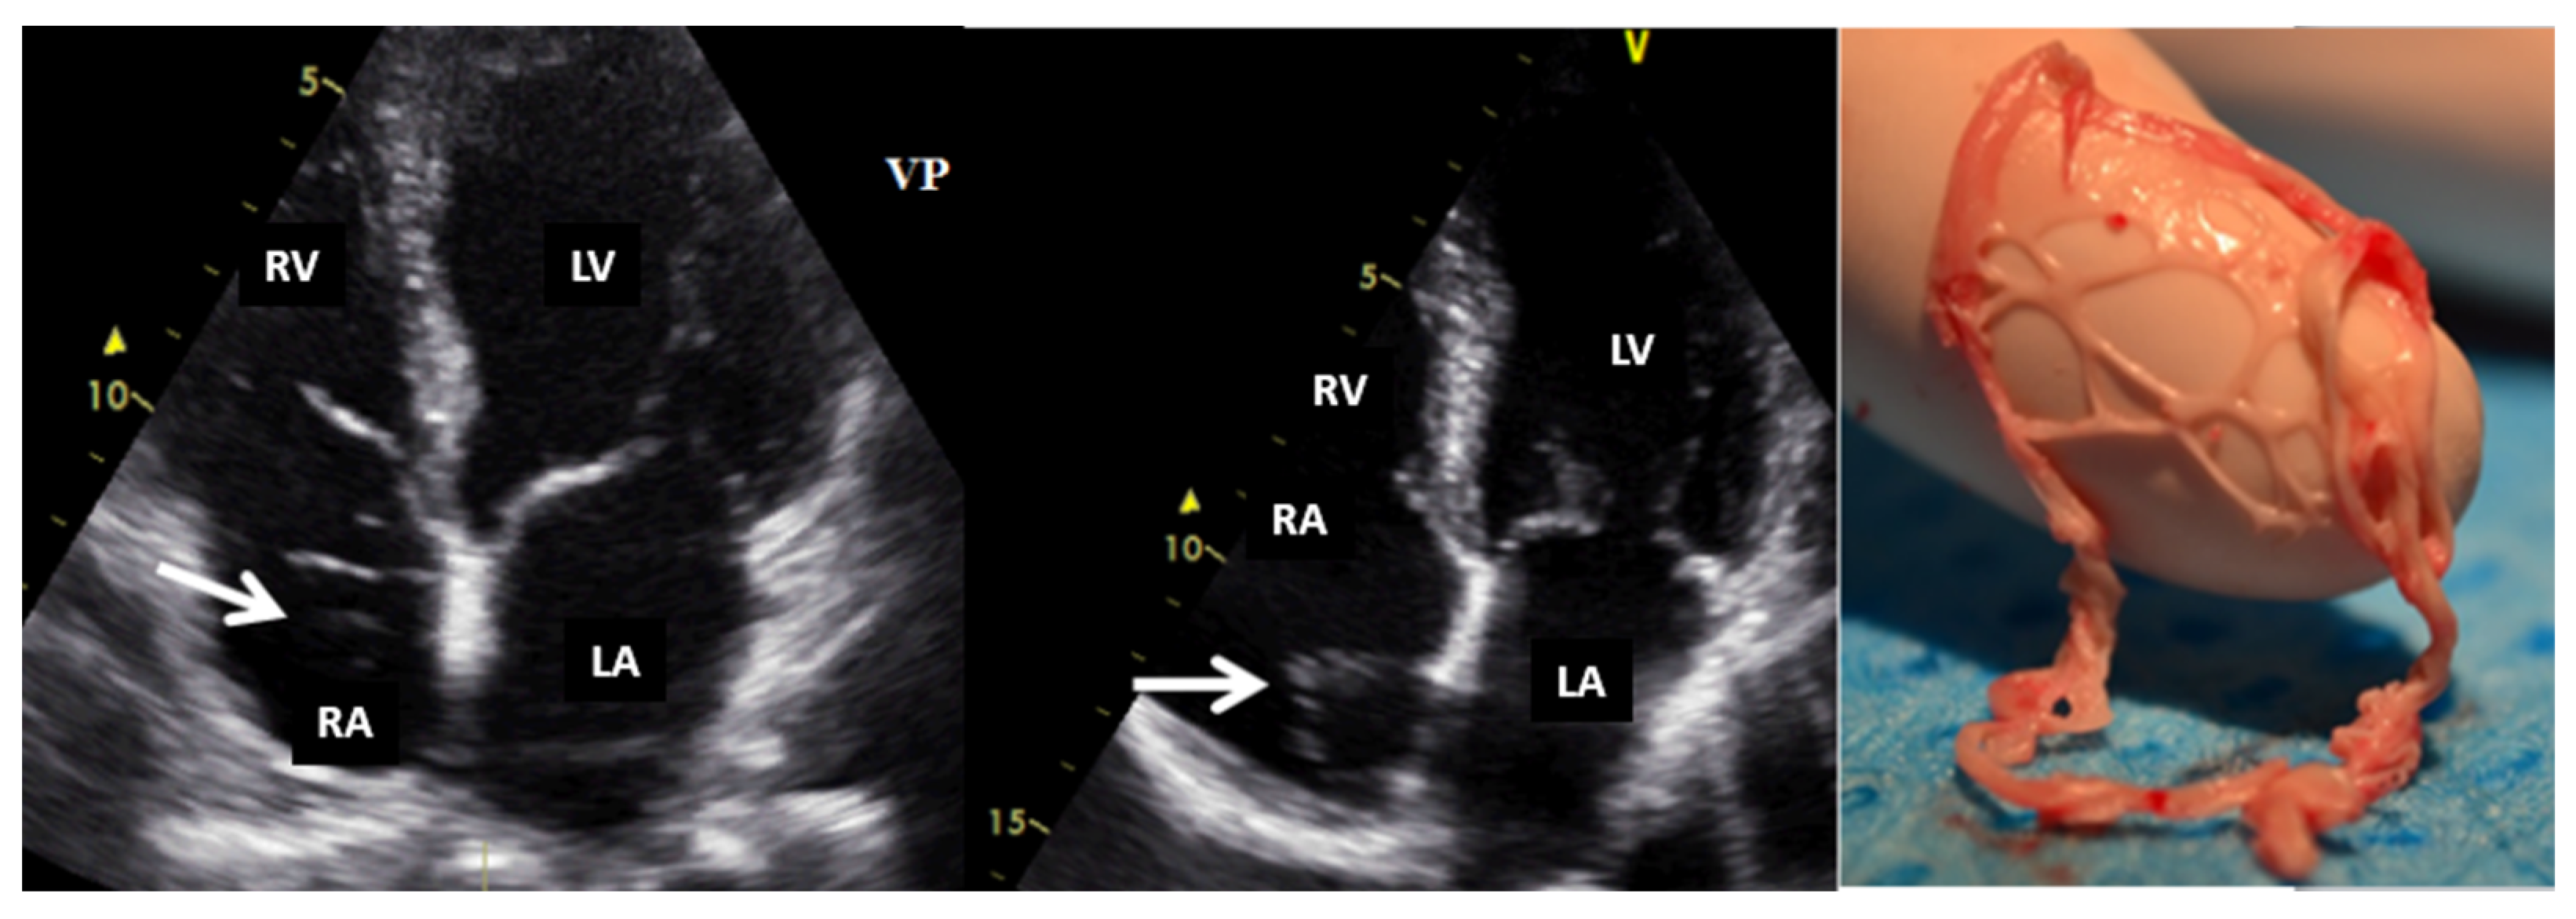

Echocardiography with ultrasound-enhancing agents is the best modality for tissue characterization [13]. Two-dimensional TTE may sometimes overrate the size of myxomas or very soft tumors (myxoid- or gelatinous-type masses) due to their distensibility, mobility, or irregular shape, especially when compared to three-dimensional TEE. However, the size of the tumor is appropriately assessed by TTE in most cases. The site and type of tumor attachment, a useful clue to define the type of cardiac tumor, could be determined easily by TEE (especially 3D). For example, right atrium angiosarcomas, described as heterogenic masses with central necrosis on CT or CMR [13], could be attached to any part of the right atrial wall, while myxomas (Figure 2) are usually situated in the fossa ovalis region of the atrial septum (most frequently on the left side).

Figure 2.

Two−dimensional transesophageal echocardiography (short-axis view at the level of the great vessels) showing a huge inhomogeneous mass (arrow) attached to the interatrial septum crossing the tricuspid valve (which, upon histology diagnosis, was a myxoma). AO, aorta; IAS, interatrial septum; LA, left atrium; RA, right atrium; RV, right ventricle.